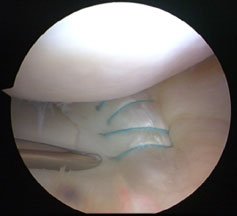

The approach is that if someone is in pain and the knee is very swollen then it is a limited examination, and one has to be realistic. With the knee out fully straight we call that zero degrees, and that is the starting point. And then we see how far the patient can bend the knee (flex) and we compare this with the normal side. The most one can normally flex the knee is about 140 degrees. The patient frequently holds the knee in a slightly bent position and may have a very much reduced range of movement, and will often struggle to get the knee out fully straight. If it is impossible to get the knee out fully straight as part of the examination and the knee is truly ‘locked’ as we call it, then that quite commonly is due to one of the menisci (usually the medial) tearing and flipping into the middle of the knee, and that is called a ‘bucket handle tear’. A bucket handle tear is relatively common, and the story is usually that of a young sportsman who has an injury, the knee swells up immediately or perhaps several hours later, they come into A&E and they cannot fully straighten their leg.

A meniscal tear is a relatively important diagnosis to make, and more importantly it is a relatively important problem to sort out acutely (a) because it is really painful and (b) because the best time to fix the meniscus is in that early period just after the knee has been injured (within six weeks). If someone comes in with a locked knee though, you don’t leave them stewing for six weeks - they should be admitted straight away. You can get an MRI – there is no harm in getting additional information – but the knee needs to be unlocked and generally speaking that means an arthroscopy, the flipped meniscus is reduced and it is stitched back into postion if you have the skills to do that. We routinely now carry out meniscal repair in that sort of situation.